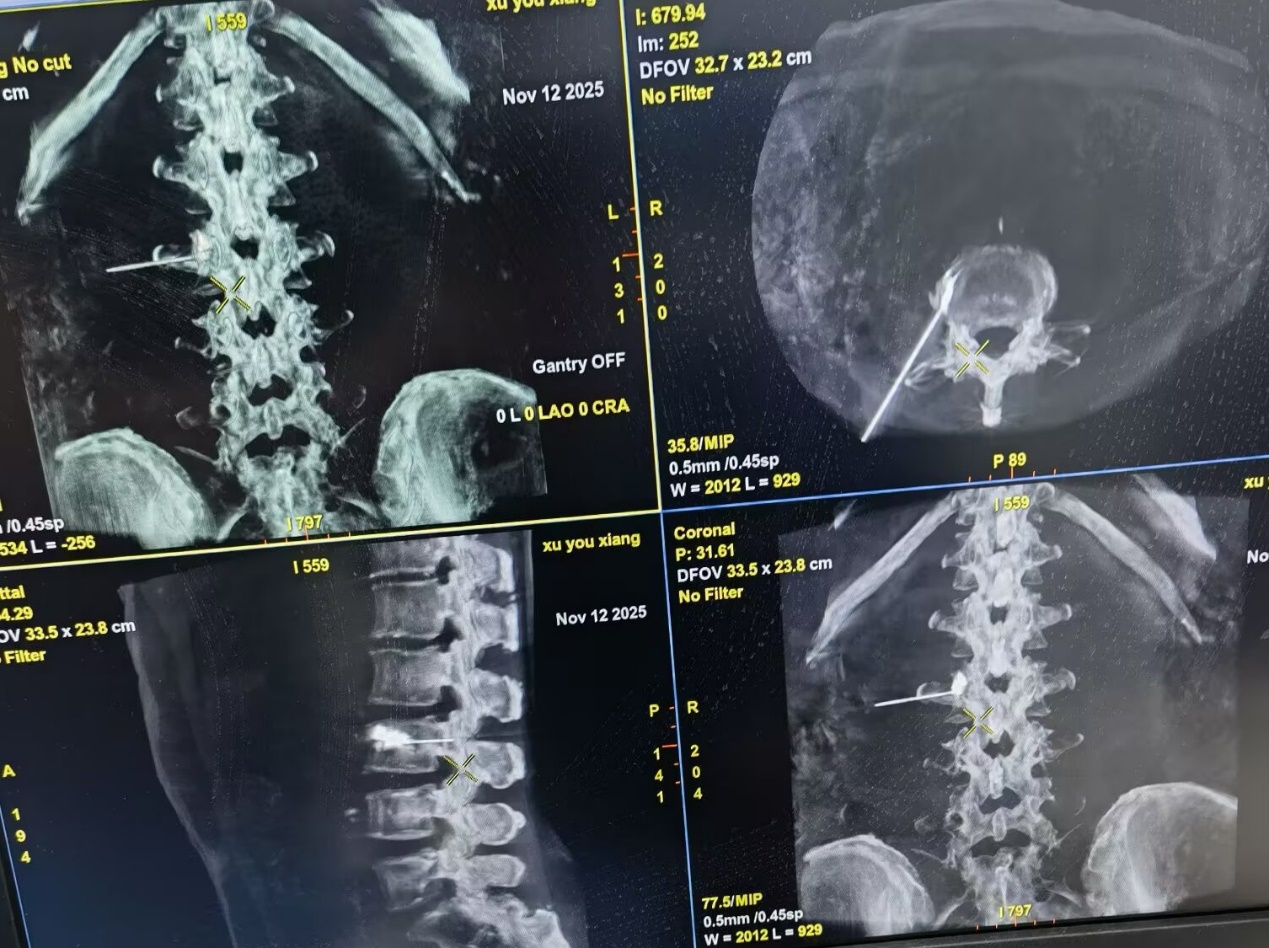

术中,疼痛科医务人员紧密配合,在DSA设备引导下,使用射频穿刺针从患侧腰部刺入,根据影像调整刺入角度和深度,避开骨质增生,精准定位到腰交感神经节附近靶点(如下图),给予造影确认无误后,给予患者行腰交感神经节射频治疗,治疗完毕后10余分钟,患者自觉右下肢微热,疼痛缓解。经治疗后,患者下肢发凉、疼痛、多汗症状明显改善,对此疗效表示相当满意。